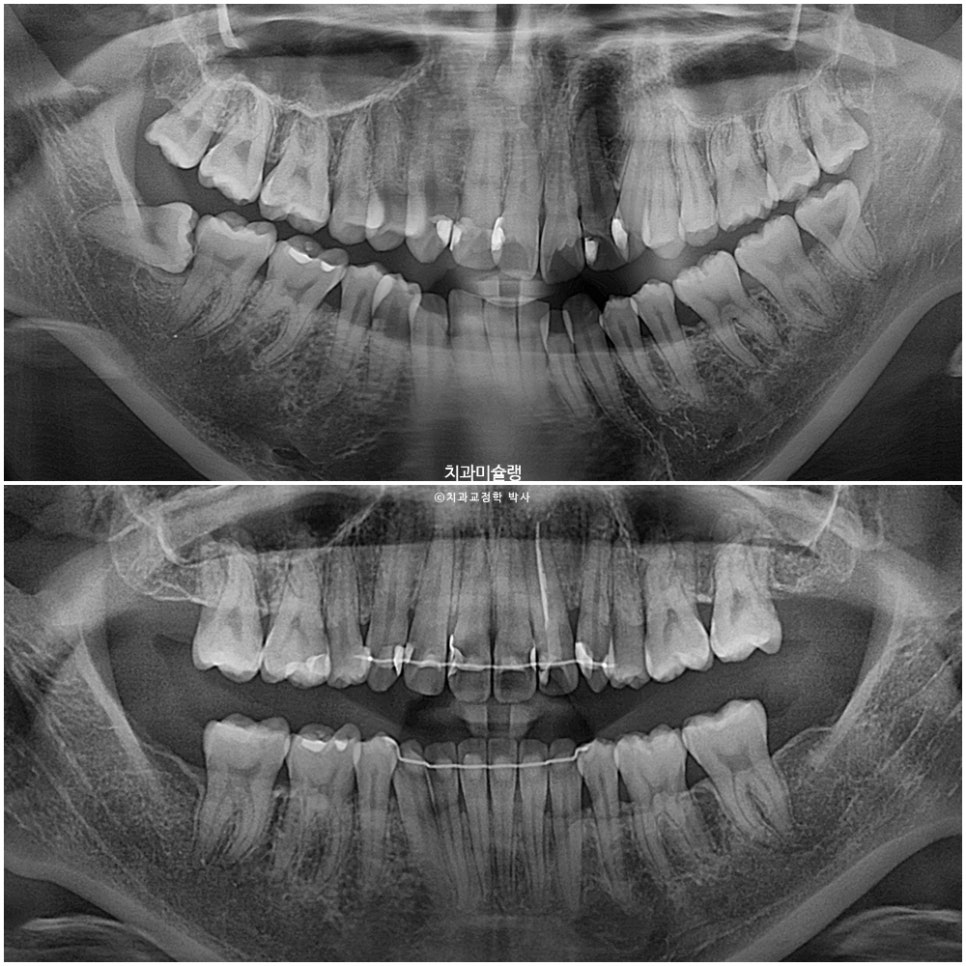

앞니뿐 아니라 어금니에도 여기저기 충치가 보입니다.

인비절라인 치료 도중이라도 레진이나 인레이와 같은 충치치료는 가능합니다.

첫번째 작은어금니와 두번째 작은어금니 중에서 충치있는 치아 위주로 발치치아를 선택했으며 첫 세트 장치는 78개가 나왔습니다.

치근흡수는 없으며 어금니 쓰러짐 없이 잘 마무리 되었습니다.

돌출감의 해소와 앞니 각도 변화는 전후 엑스레이에서 잘 보입니다.